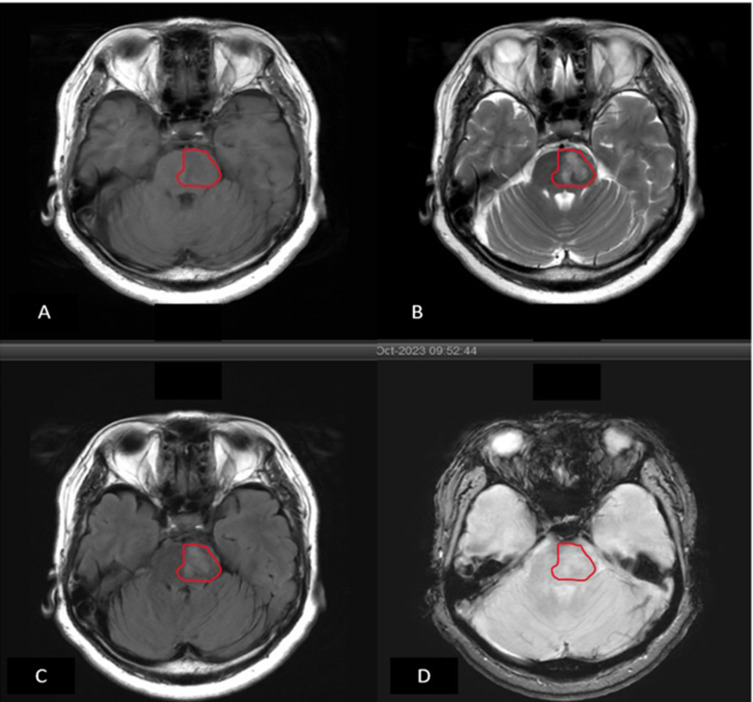

Ischemic stroke is the second leading cause of mortality and morbidity worldwide. Due to the urgency of implementing immediate therapy, acute stroke necessitates prompt diagnosis. The current gold standards for vascular imaging in stroke include computed tomography angiography (CTA), digital subtraction angiography (DSA) and magnetic resonance angiography (MRA). However, the contrast agents used in these methods can be costly and pose risks for patients with renal impairment or allergies. The aim of this paper is to provide a comprehensive overview of current MRI techniques and sequences for evaluating ischemic stroke, emphasizing the importance of non-contrast options and their clinical implications for radiologists in the diagnosis and management of ischemic stroke. Standard MRI sequences-such as T1-weighted imaging (T1WI), T2-weighted imaging (T2WI), fluid-attenuated inversion recovery (FLAIR), diffusion-weighted imaging (DWI), DWI-FLAIR mismatch, and apparent diffusion coefficient (ADC)-are essential for determining infarct location, volume, and age. Additionally, incorporating susceptibility-weighted imaging (SWI) sequence aids in identifying signs of hemorrhagic transformation within the infarcted region. Advanced techniques like arterial spin labeling (ASL) can serve as a non-contrast alternative for mapping cerebral blood flow (CBF) and allowing for comparison between infarcted and healthy brain areas. Adding ASL to the routine sequence allows ASL-DWI mismatch analysis that is useful for quantifying salvageable tissue volume and facilitate timely recanalization, while time-of-flight (TOF) MRA and magnetic resonance venography (MRV) help assess venous thrombosis, stenosis, or arterial occlusions. Finally, MR spectroscopy can provide insights into critical brain metabolites, including N-acetylaspartate (NAA), and lactate (Lac) to determine patient prognosis. Current MRI technology provides a myriad of sequence options for the comprehensive evaluation of ischemic stroke without the need for contrast material. A thorough understanding of the advantages and limitations of each sequence is crucial for its optimal implementation in diagnosis and treatment.